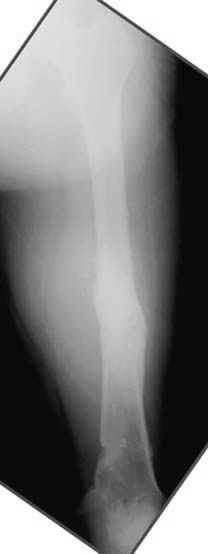

Отправитель: Djoldas Kuldjanov 23 Ноябрь 2004, 18:21

пластическая модель; и коррекция бедра аппаратом Илизарова.

Имею другие снимки тоже, получится как отчет о моей работе.

Узкий к-м канал - тонкий гвоздь- усталостный перелом дистальных винтов - развитие нестабильности и как ее результат остеолиз вокруг гвоздя - деформация анатомической оси бедра. Похоже, что я понял почему аппарат, а не новый гвоздь:-)